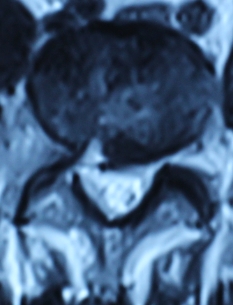

1.患者邹某,男,79岁,因“腰痛双下肢疼痛1年余,加重并间歇性跛行2月”于2014年3月26日入院。入院见患者腰痛病双下肢疼痛、麻木,间歇性跛行,行走约10余米,休息后略缓解。查:直腿抬高试验左40°(+),右55°(+),加强试验(+),腰背伸试验阳性。双侧膝腱未引出,跟腱反射减弱,双侧踇背伸肌力Ⅳ级。入院后诊断为腰椎管狭窄症。患者既往患糖尿病、高血压、冠心病病史。入院后完善检查,明确诊断,请相关科室会诊后认为手术风险极大。经科室讨论后行经皮椎间孔镜下髓核摘除并椎管扩大成形术,手术麻醉方式为局麻。于2014年3月29日行手术治疗,经椎间孔入路椎间孔镜下髓核摘除椎管扩大成形术。手术顺利,术中无出血,手术时间约40min。术中可与患者交流。术后患者即可感双下肢无疼痛,第二天佩戴腰围下地活动后双下肢无不适。术后半年复查腰椎MRI示突出髓核已摘除,神经根无受压。术后随访1年,患者目前病情恢复良好,无下肢疼痛、麻木,无间歇性跛行。

术前腰椎MRI